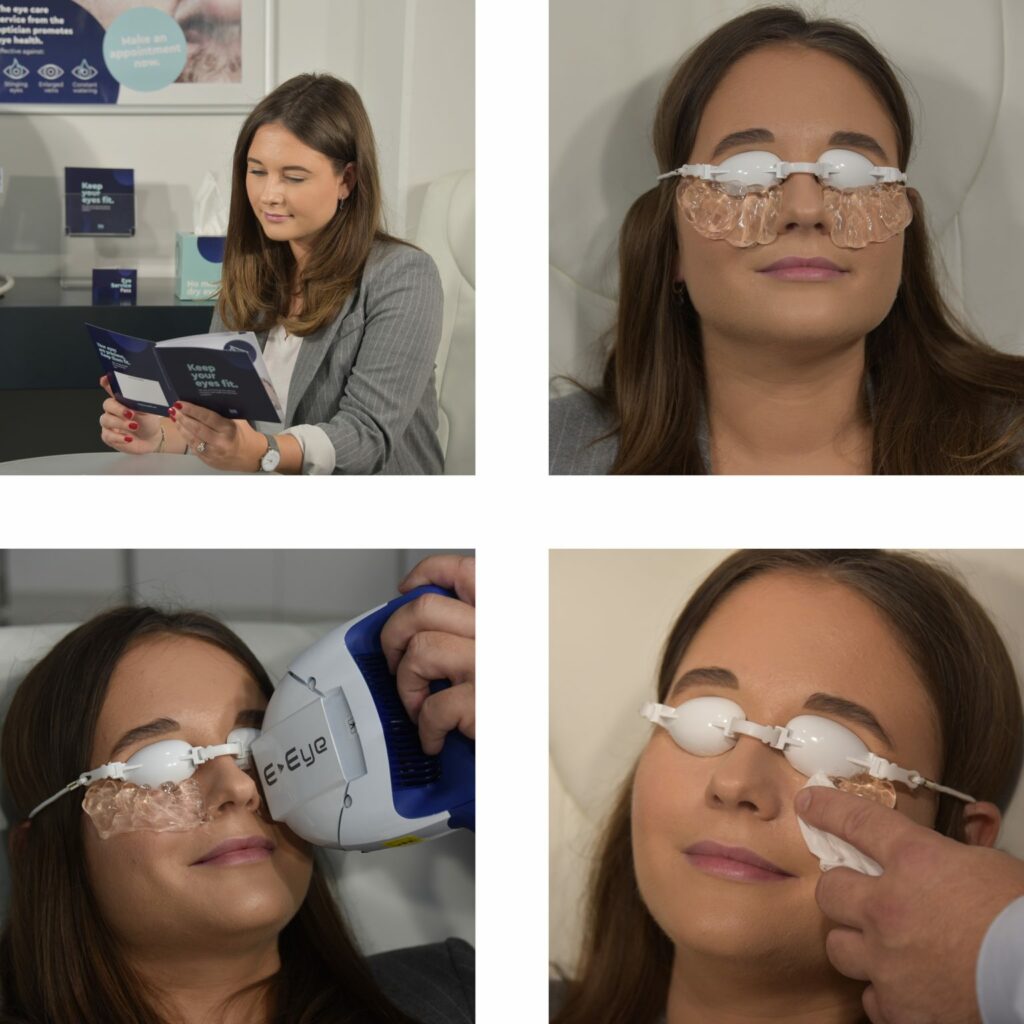

Intense Regulated Pulse Light (IRPL) therapy is one of the latest treatments for dry eyes. It’s particularly effective in treating Meibomian Gland Dysfunction (MGD), the most common cause of chronic dry eyes.

IRPL targets all aspects of MGD by:

IRPL produces perfectly calibrated light pulses that target the meibomian glands. These light pulses result in a neurological stimulation of the parasympathetic nerve which supplies the meibomian glands.

The treatment protocol is short and efficient, with three to four treatments depending on the severity of the condition:

Treatment #1: Day 1

Treatment #2: (2 weeks later): Day 15

Treatment #3: (30 days later): Day 45

Treatment #4: (if needed, 30 days later): Day 75

Most patients feel an improvement within the first day after the treatment. The nerve stimulation from IRPL helps the meibomian glands function normally within a few hours. The effects of the treatments are cumulative, which is why it is important to follow the treatment protocol.

The results can last anywhere from 6 months to 3 years, depending on your eyes. If your symptoms do start to come back, your ophthalmologist will likely recommend more sessions.

For long term results, you should have at least 3 treatment sessions and follow any recommendations from your ophthalmologist.